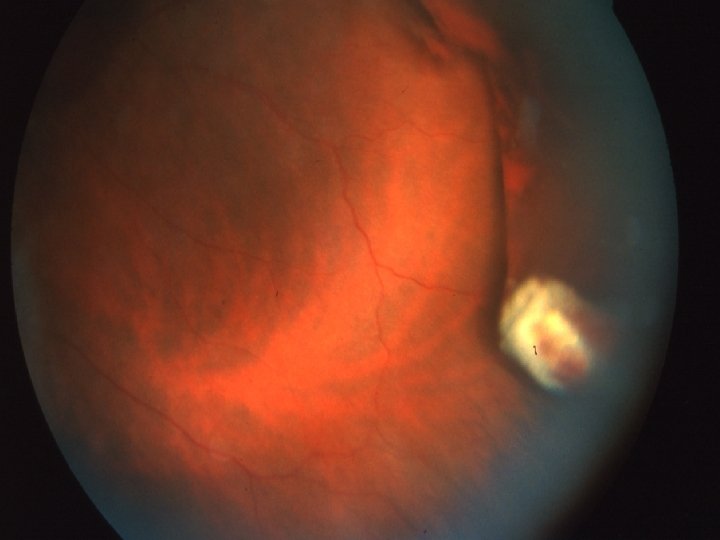

Traumatologie et Brûlures oculaires 2 - Contusions du globe Le syndrôme traumatique du S. postérieur Ruptures choroïdiennes Stries jaunâtres bordées d’une hémorragie BAV ++ si touche la région maculaire Décollement de rétine Désinsertion à l’ora ou déchirure, peut apparaître plusieurs jours après le trauma BAV progressive, ttt chirurgical